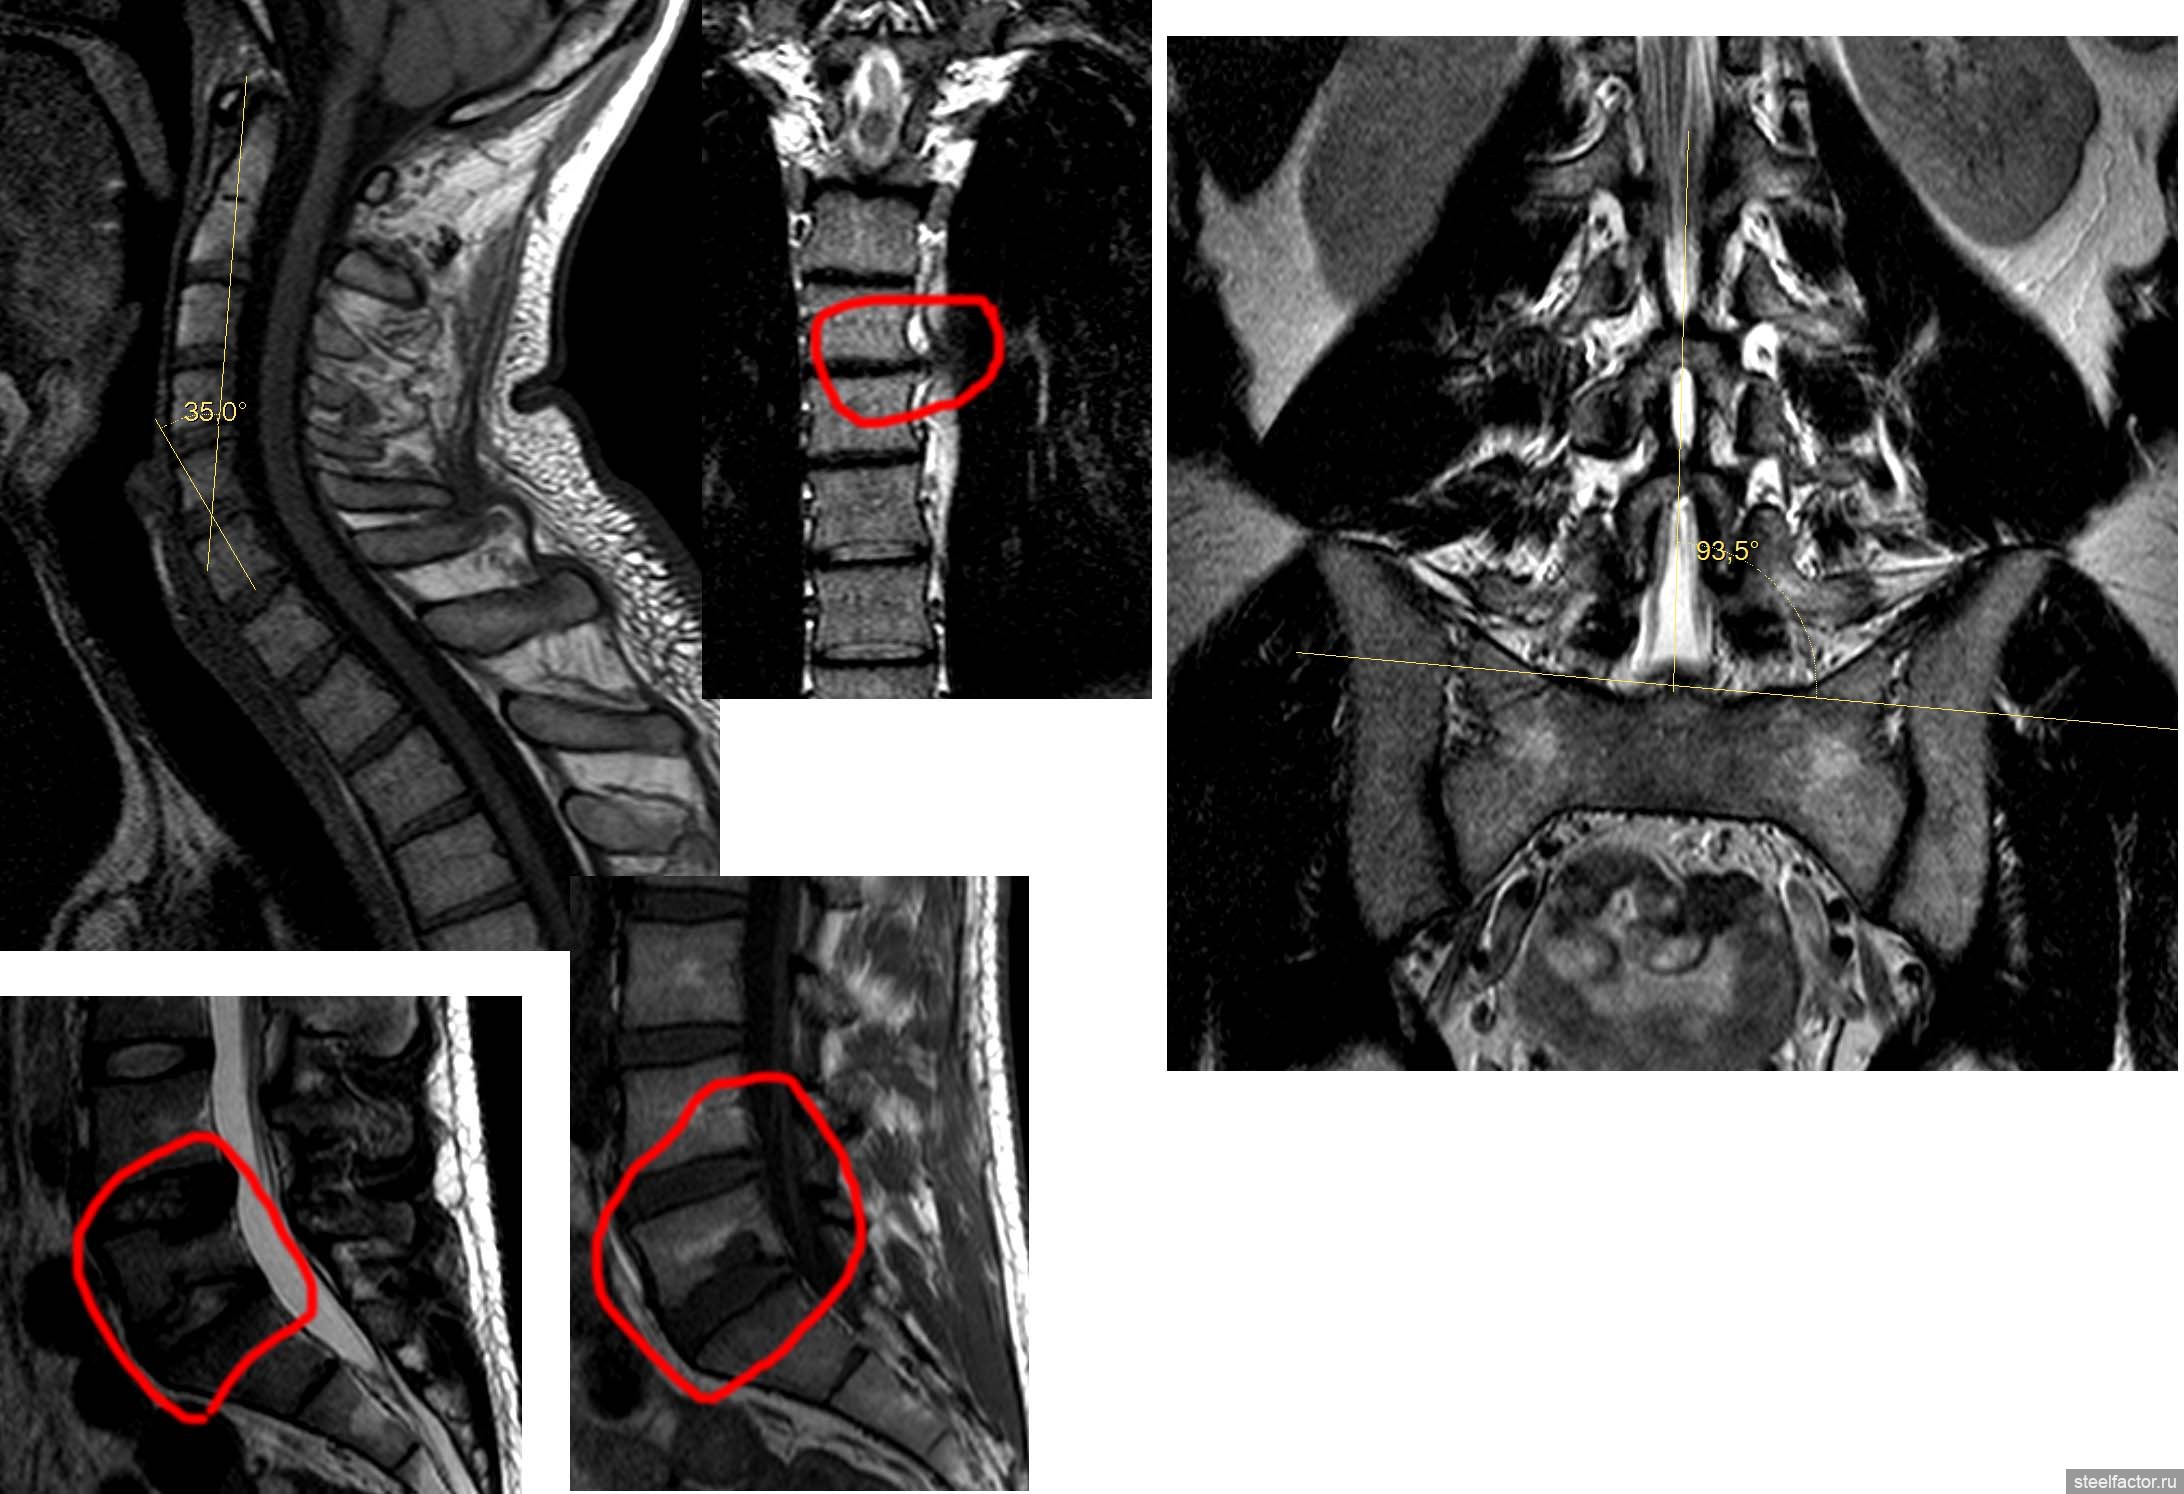

у тебя изменения позвонков, это не очень хорошо, но с этим уже ничего не сделаешь.

В грудном у тебя грыжа слева. На снимках видно.

В поясничном отделе жопа с одним позвонком, то же видно, посмотри. Я в их номерах не силен.

Сфоткайся в полный рост сбоку.

По горбатости - на скрине шейный отдел, я признаю, что мог неграмотно померить угол, но отклонения есть.